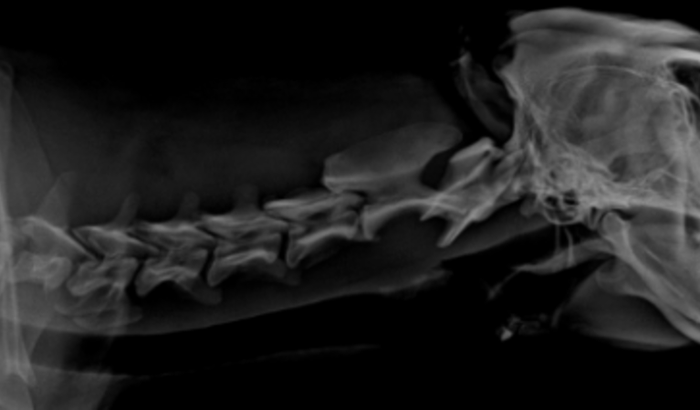

Eu sou a LISIANE criei essa vaquinha pq preciso arrecadar 1.700,00 para realização de um exame ressonância de coluna cervical para o caramelo, ele tem muita dor e necessita realizar esse exame para possível cirurgia de calcificação de vértebra na cervical, nesse valor está incluído o exame e despesas para levá-lo a clínica em Porto Alegre.